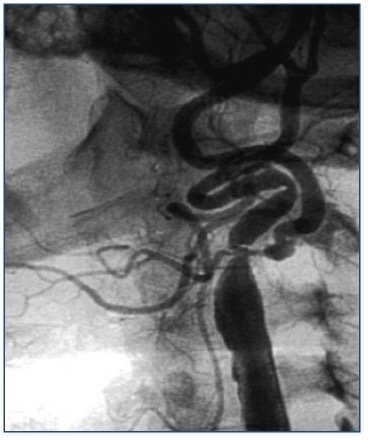

Resim: Karotis darlığında stent uygulaması

Stent için uygun olmayan cerrahi tedavi gerektiren hastalar

1. Ana karotis arter çıkışında büklümlü olması

2. İnternal karotis çıkışında 90 derecelik açılanma

3. Hem İnternal, hem de eksternal karotis’de ciddi darlık

4. İnternal karotisin sağa açılı çıkışı

5. Ana ve İnternal/Eksternal karotis stenozu

6. İnternal karotiste ‘de 3 loop